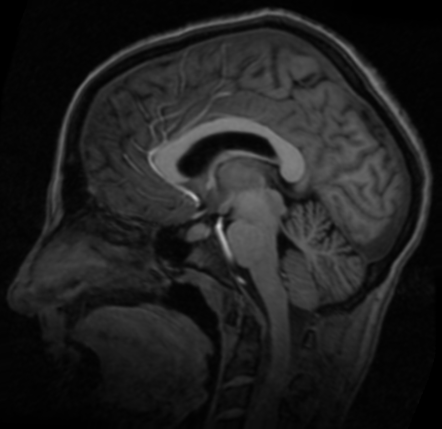

使用以上实现的配准方法,对脑部图像进行配准。

参考图像